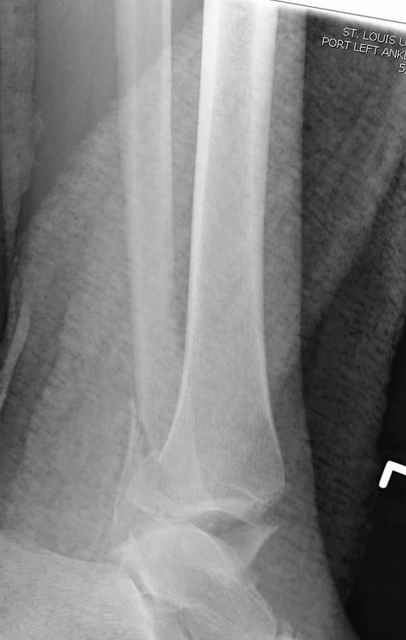

Я посоветовал, как бы это сделал я в своих условиях, единственное, что я бы хотел еще сказать - не торопился бы с первичным артродезом - нередко

РГграмма выглядит ......... нет слов, а больной ходит с полной нагрузкой и без болей с приемлемым объемом движений г\ст сустава для ходьбы

На прямой проекции послеоперационного Рг макроскопически все выглядит очень анатомично, при микроскопическом ( :-)) ) рассмотрении можно все-таки заметить вальгизацию тарана, суставная щель в латеральном отделе сустава несколько уже , чем в медиальном при отсутствии латерального смещения тарана. У меня был аналогичный случай (без LISS , без мини доступа) с вальгусным наклоном тарана при восстановленном ankle mortise при последовательном наблюдении с интервалами в 6-8 недель в послеоперационном периоде отмечалось прогрессирующее сужение суставной щели в латеральном отделе сустава, закончившееся посттравматическим ОА, к счастью боли умеренные, купируемые аналгетиками или своими эндорфинами:-))(активная пациентка, у которой нет времени на болезни....) Какова жизненная ситуация в приведенном вами случае? И последнее, что я хотел бы прояснить для себя - фиксация внутренней лодыжки: я обычно комбинирую фиксацию компрессирующим винтом со спицей - по идее ротационная стабильность должна быть лучше, чем один винт, каковы ваши наблюдения в этом плане?